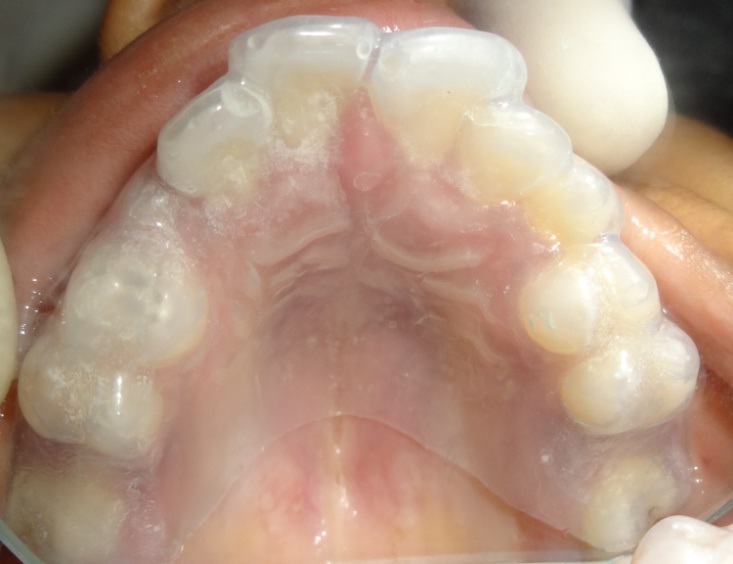

Presently, the child is 11-year-old and parents demanded fabrication of another mouth guard. Examination showed low IQ where patient had a delayed response to commands, scars on skin [Table/Fig-1], deformed interphalangeal joints of fingers [Table/Fig-1] and missing big toe of left foot [Table/Fig-2]. Attrited lower incisors [Table/Fig-3] causing loss of support for lower lip resulting in lip trap and deep labio-lingual sulcus [Table/Fig-4]. Tongue was severely affected with the loss of the tip with irregular margins [Table/Fig-5]. Permanent first molars required extraction to which the parents didn’t agree [Table/Fig-3]. Thus, an impression was made of upper and lower arch to fabricate a mouth guard [Table/Fig-6,7]. Try-in was done and the parents were given instructions regarding the care of the mouth guard. The patient is on follow-up.

Maxillary casts used for the fabrication of mouth guard.

Mouth guard placed in the maxillary arch.